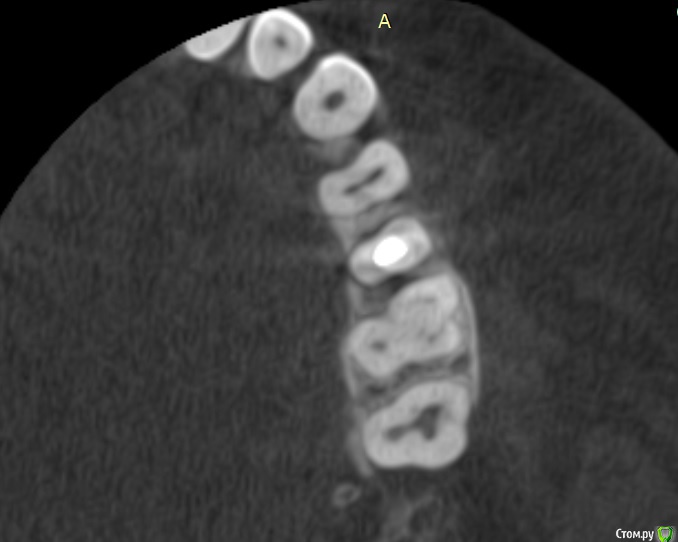

Verasss Опубликовано 8 октября, 2016 Автор Поделиться Опубликовано 8 октября, 2016 КТ от 08.09. Извините, что в таком виде, надо менять ОЗУ. Ссылка на комментарий

DmitrySH Опубликовано 8 октября, 2016 Поделиться Опубликовано 8 октября, 2016 В таком виде КТ малоинформативно. Но гайморита нет. Ссылка на комментарий

Verasss Опубликовано 28 октября, 2016 Автор Поделиться Опубликовано 28 октября, 2016 Добрый вечер! Ещё раз попытаюсь прикрепить скриншоты КТ от сентября. Если качество совсем не устраивает, подскажите, пожалуйста, какие сделать снимки?К сожалению, программа не позволяет вывести снимки на полный экран и заскриншотить в более хорошем качестве. Ссылка на комментарий

Verasss Опубликовано 28 октября, 2016 Автор Поделиться Опубликовано 28 октября, 2016 еще снимки Ссылка на комментарий

Verasss Опубликовано 28 октября, 2016 Автор Поделиться Опубликовано 28 октября, 2016 и еще Ссылка на комментарий